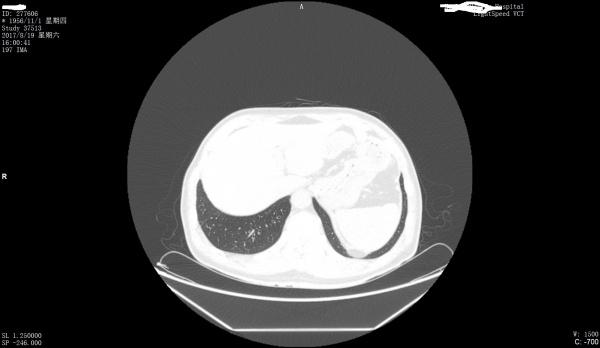

看看是否左膈肌出现胸腹膜裂孔疝

第一上传图片少,第2目前来看只能是疑似。